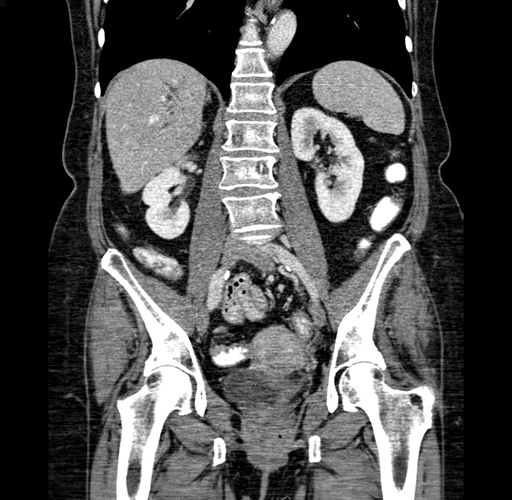

Coronal Venous